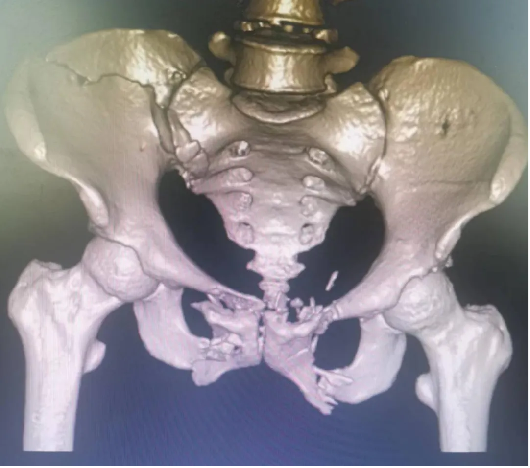

患者因外傷致骨盆前環骨折,患者難以忍(rěn)耐長期臥床及疼痛,要求(qiú)行手術治療以期早日自主翻身坐立活動。